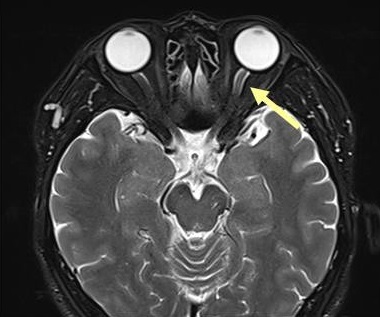

IgG4関連眼症のMRI所見は、T2強調画像で涙腺炎に加え、

- 視神経周囲組織の炎症(IgG4 眼症は視神経炎を伴う場合がある)

- 様々な眼組織に腫瘤(眼球裏面に索状の腫瘤など)

- 三叉神経(眼窩上神経と眼窩下神経)の腫大[Ophthalmic Plast Reconstr Surg. 2019 Mar/Apr;35(2):170-176.]

を認める点が、甲状腺眼症・バセドウ病眼症と異なります。造影MRIでは、いずれも増強されます。